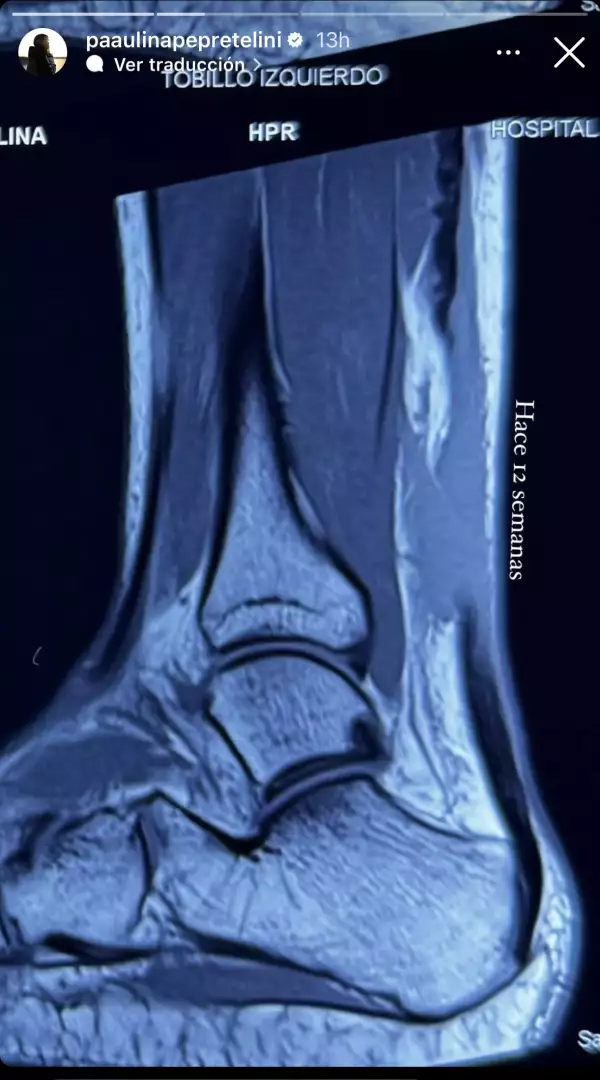

Ahora, dos meses después, parece ser que su recuperación continúa en evolución y su ánimo también. Paulina Peña está contenta porque a través de sus stories mostró como hace 12 semanas se veía la radiografía de su tobillo izquierdo y hoy parece ser que ya se encuentra mejor, incluso hasta podría bailar. Se entiende así por el emoji de aplauso que puso y al lado uno de bailarín.